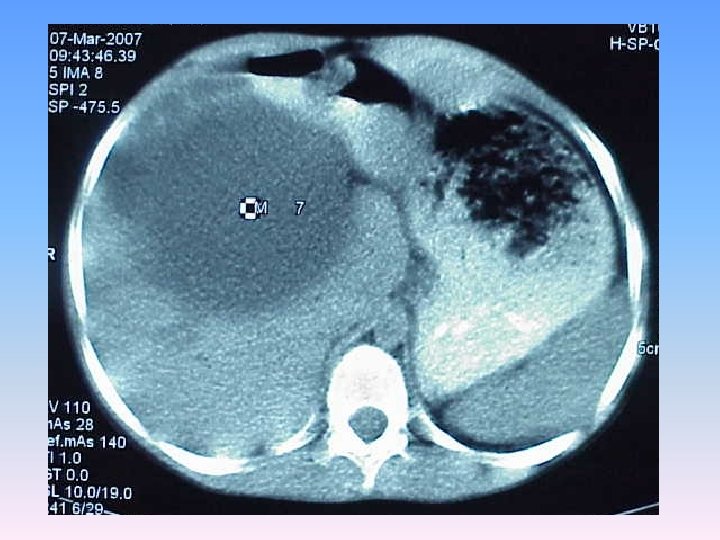

Abdominal CT Scan § A regular lobulated cystic mass in right lobe of liver (120 x 120) without calcification causing dilatation of intra & extra biliary ducts.

MRCP & MRI § Huge thicked wall cystic mass (140 x 120 mm), at the portahepatis that seems connected to biliary tree and gall bladder, resulted in severe dilatation of intra hepatic bile ducts and displaced right kidney posteriorly. § Spleen, kidneys, bowel loops and abdominal wall are normal. § Finding could be due to congenital anomalies like choledocal cyst, Duplication cyst, mesenteric cyst and hydatid cyst are in DDx.

Surgery report § There was a mass(10 x 20 cm) in hilum of liver which had compressed the duodenum anteroinferiorly. It was not resectable because of extension and adhesion to the mesocolon & stomach. § Gall bladder was bilobulated. § Stomach , intestine & uterus were normal. § Cyst was draineged which was full of bile. § Cystodoudenostomy to D 2 was done.